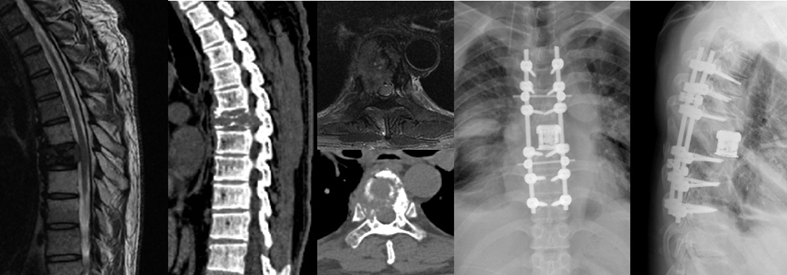

骨是恶性肿瘤常见的转移部位,而脊柱又是骨转移最常见的部位,作为脊柱外科医生,接下来我们就来和大家聊聊脊柱转移性肿瘤的常见表现以及治疗方法。

脊柱转移性肿瘤的危害主要在于会产生轻微外伤甚至无外伤情况下的病理性骨折,从而导致剧烈的疼痛。如果肿瘤或骨折块直接压迫神经脊髓就会导致肢体的疼痛、麻木、肌力下降、大小便障碍等,肿瘤严重压迫者甚至可能截瘫。这些都会给患者带来巨大的痛苦,为家庭带来沉重的负担。因此,我们针对脊柱转移性肿瘤的治疗就是为了避免发生以上情况而采取的主动出击的方式。

那么,我们如何治疗脊柱转移性肿瘤呢?其中一个很重要的措施就是手术。近年来,针对脊柱转移性肿瘤,已有了微创椎体成形术、微创经皮内固定术、微创椎管减压经皮内固定术、椎管减压肿瘤脊髓神经分离术、肿瘤大块切除术等解决方法,更是有了全脊椎整块切除术这一脊柱外科最高难度及风险系数的手术。